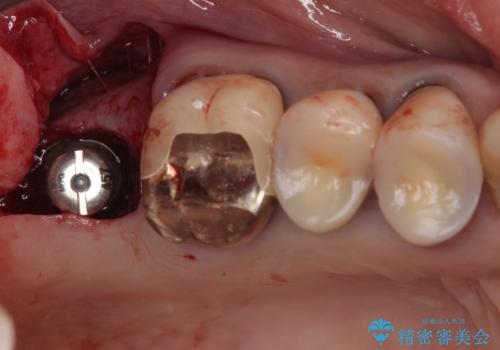

抜歯後2ヶ月でのインプラント埋入を行いましたが、骨の再生は不十分でした。

骨量は不十分でしたが、デンサーバーを用いることで無事に埋入することができ、その後は速やかに補綴治療を行うことができました。